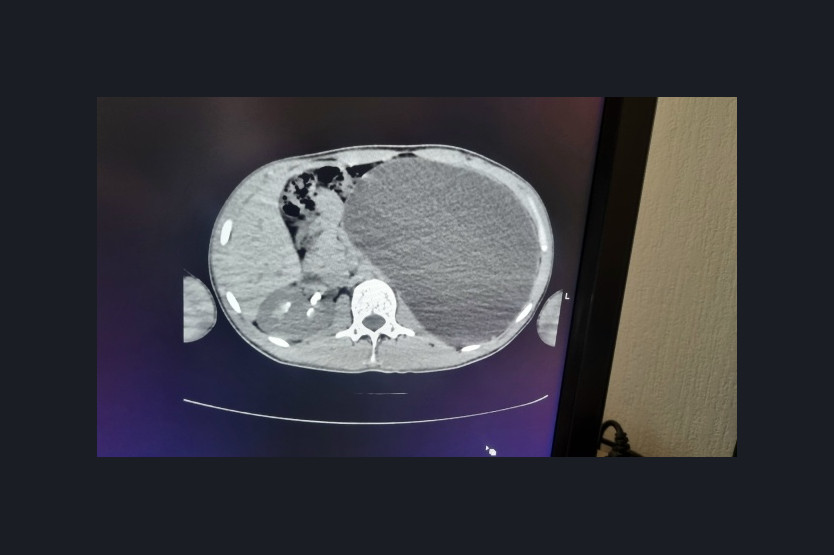

Врачи направили его в детскую клиническую больницу № 1, где обследование подтвердило наличие объемного образования в брюшной полости. Оказалось, что левая почка увеличена настолько сильно, что заняла практически весь объем живота и угрожающе сдавливала соседние органы. Врачи назвали ситуацию бомбой замедленного действия, ведь любое физическое воздействие могло спровоцировать разрыв почки.

«У нашего пациента почка достигла размеров пятилитровой бутылки! Она занимала почти весь объем живота и давила на все соседние органы. Это была настоящая «бомба замедленного действия»: любая травма, случайный удар в живот – и мешок мог разорваться внутри», – рассказали в ДГКБ № 1.

Во время срочной операции хирурги извлекли поражённую почку размером с пятилитровую бутылку, предварительно откачивая собравшуюся жидкость через небольшие разрезы. Операция прошла успешно, молодой человек восстанавливается и вскоре вернется к нормальной жизни и выйдет на работу.